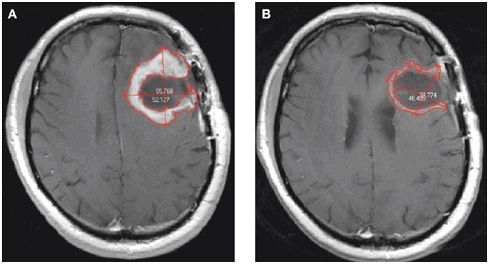

Μια από τις συχνότερες μορφές καρκίνου του εγκεφάλου

Το γλοίωμα είναι μια από τις συχνότερες μορφές καρκίνου του εγκεφάλου. Ξεκινά από τα κύτταρα που περιβάλλουν τα νευρικά κύτταρα και βοηθούν τη λειτουργία τους. Συνήθως, το γλοίωμα διαγιγνώσκεται σε μεσήλικες και προς το παρόν δεν υπάρχει θεραπεία που να συντελεί σε μακροπρόθεσμη επιβίωση.